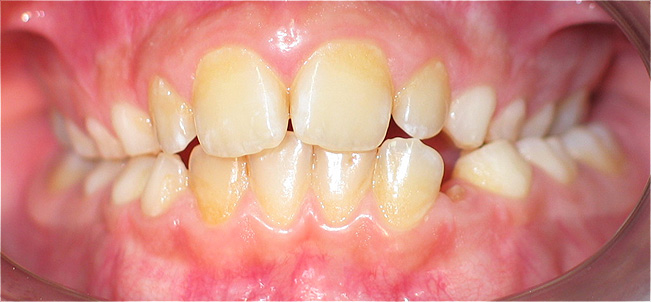

Apinhamento dentário com os dentes caninos em desoclusão (classe II, divisão 2).

![]() |

Após dois anos de tratamento ortodôntico.